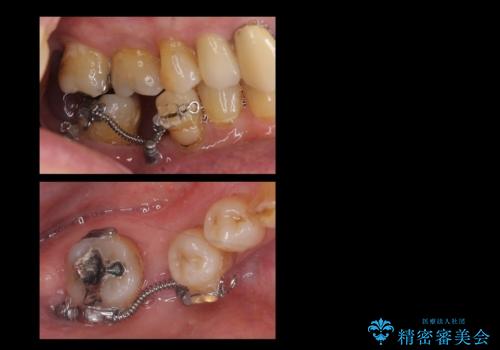

60代男性 奥歯のブリッジ 倒れこんでいる奥歯を部分矯正

- 右下の親知らずが咬むと痛いとのことでした。

親知らずを抜いて、倒れこんでいる手前の歯を矯正治療で移動させ、ブリッジにしました。

矯正治療をしなければ、倒れこんでいる影響で手前の奥歯も含めて歯周病で悪化してしまうため、しっかり起こして治療をしました。